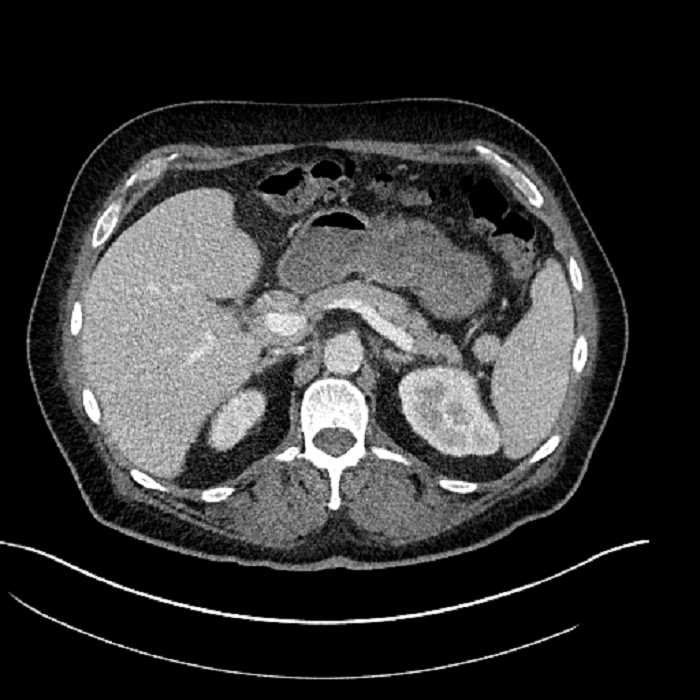

• Large fluid density structure in hepatic segments 7 and 8 measuring 10 x 7 x 7 cm with internal septation and circumferential ill-defined low density compatible with edema

• Clearly marginated fluid density structure in segment 7 and several other scattered tiny hypodensities, which likely represent cysts

• Mild mural thickening of a segment of the sigmoid colon with adjacent fat stranding and a 1.5 cm fluid and gas collection along the tip of an inflamed diverticulum

• Loss of the normal fat plane between this collection and adjacent loops of small bowel, which demonstrate mural thickening

Acute sigmoid diverticulitis complicated by a small contained perforation and a large abscess in the right hepatic lobe. Additional small subcapsular abscesses along the anterior margin of the left hepatic lobe.

• The classic CT imaging appearance is a double target sign with internal low density surrounded by an internal enhancing rim (capsule) and a low density external rim (edema)

Hepatic abscess showing the double target sign with low density internally surrounded by a thin inner enhancing rim (red arrow) and ill-defined outer low density rim (yellow arrow). Blue arrow indicates an internal septation. Red arrows: additional smaller subcapsular abscesses. Red arrow: focal contained perforation associated with diverticulitis.